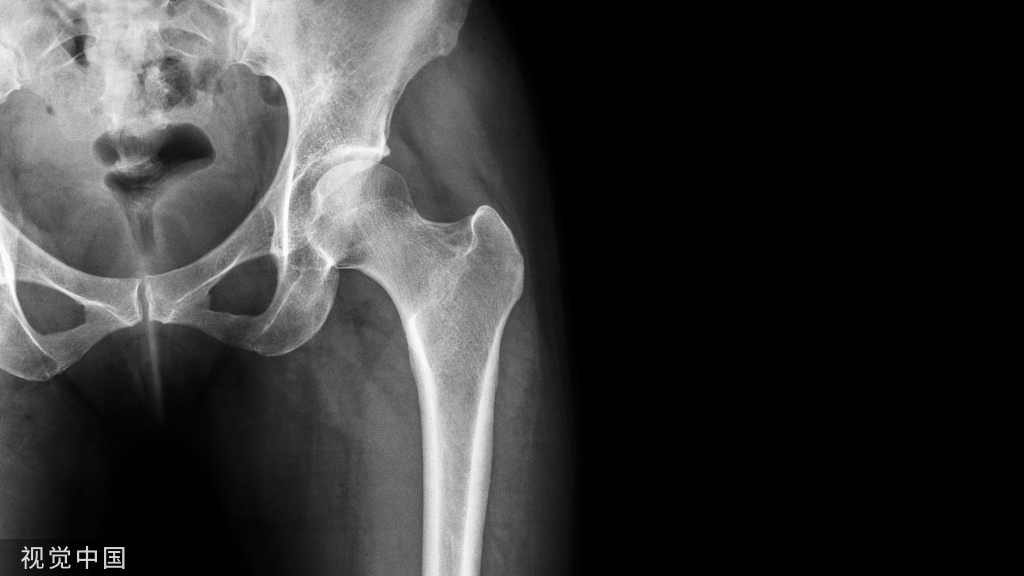

骨骺裂是一种正常变异。它可以是单侧或双侧,最常见的部位是足的第1趾近节趾骨的骨骺。

X线平片显示骨骺见透亮状裂隙影;透亮影的边缘是可变的,可能是锐利的或不规则的。骨骺裂可保留至生长板的融合。